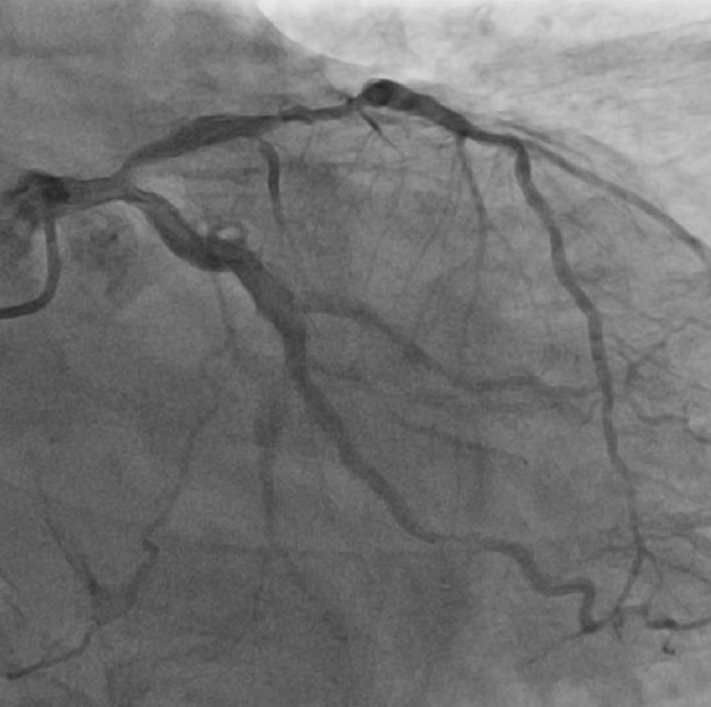

心电图提示广泛ST-T改变。经加强透析、抗感染等治疗改善心衰后,行冠脉造影提示三支病变,冠脉严重钙化,左前降支-左主干最严重,显示多处弥漫狭窄、钙化,前降支中段狭窄80%,左主干根部分叉狭窄70%狭窄。

术后造影图像